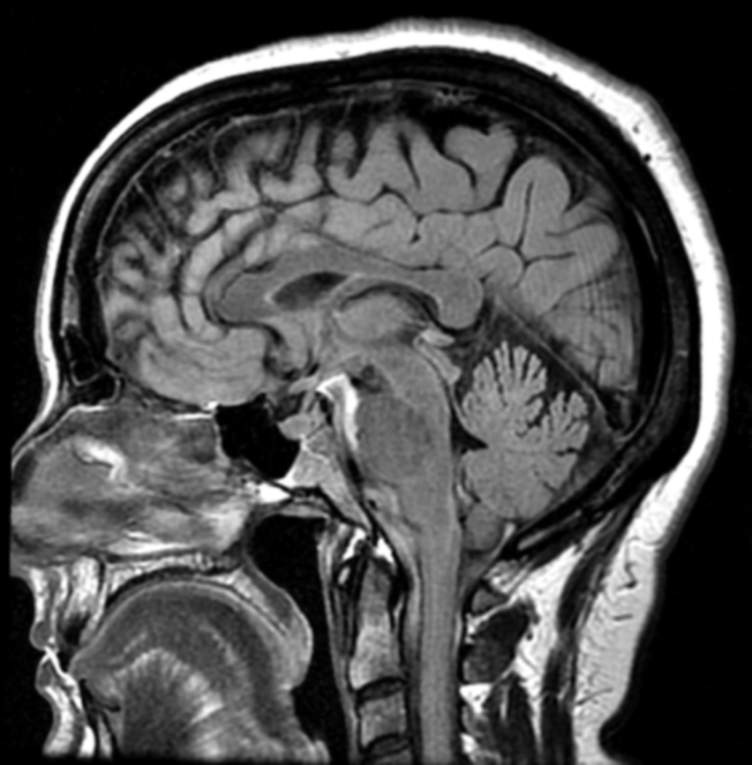

磁共振成像(MRI)是一种特殊的技术,在放射学中用于创建非常详细的身体内部部位图像,是诊断和监测多发性硬化症(MS)的重要工具。一旦确诊,患有多发性硬化症的人通常每年都要进行核磁共振扫描。一些可能有更频繁的扫描,一些不那么频繁。

核磁共振扫描仪使用强磁场产生图像。MS的标准成像协议建议使用至少3特斯拉(3T)“封闭式机器”以获得最佳效果。成像序列聚焦于静脉注射造影剂钆前后大脑和/或脊髓的白质和灰质,以增强某些解剖学特征。